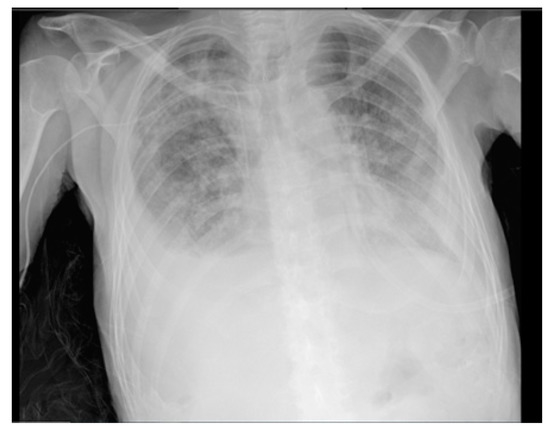

2. Case Report